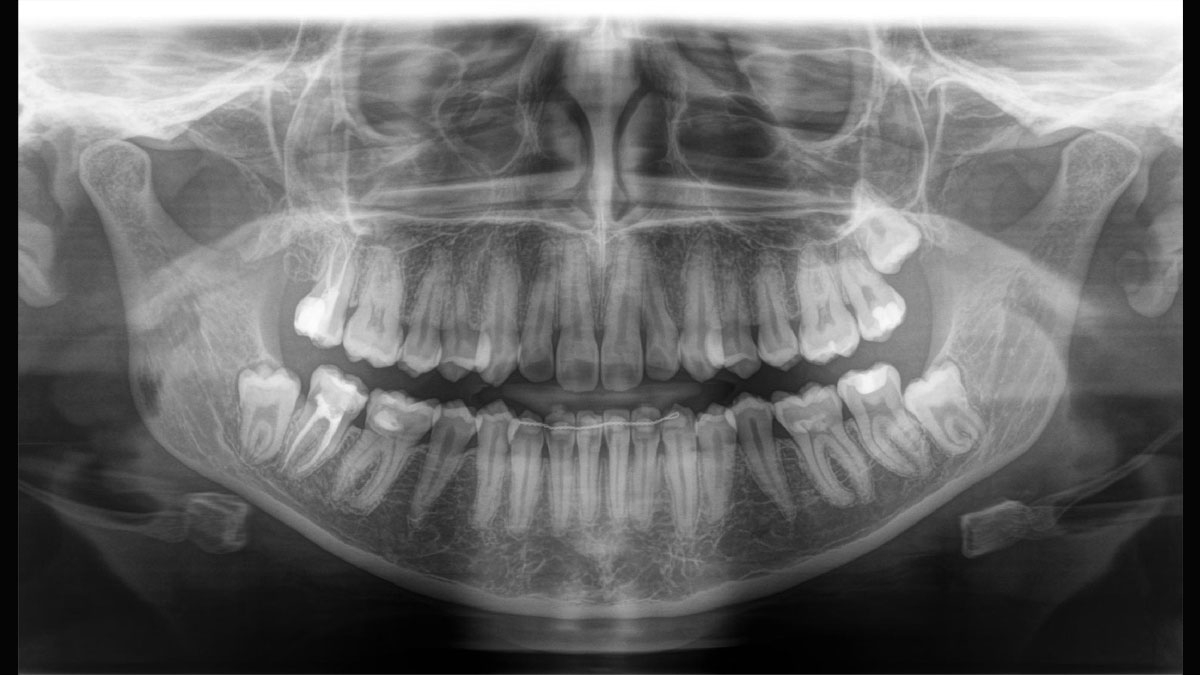

Örnek 2D Panoramik Görüntü Galerisi

Program P1

Doğrudan Dönüştürme Sensörü (DCS), panoramik görüntüleme standardını yeniden tanımlıyor. Röntgenler doğrudan elektrik sinyallerine dönüştürülür - geleneksel sistemlerin aksine, ışık dönüşümü nedeniyle sinyal kaybı olmaz. Bu da, daha iyi bir görüntü bilgisi çıktısı anlamına gelir. Sonuç, son derece düşük bir dozda bile benzersiz derecede yüksek netlik seviyesine sahip görüntülerdir.